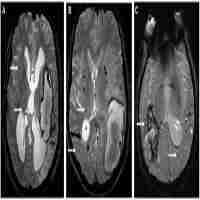

| Abstract | Introduction. The new MRI techniques introduced in the last decade allowed the detection of cerebral microbleeds (CMBs) in different groups of diseases: stroke, Alzheimer disease, vascular dementia or healthy people of advanced age. CMBs are radiologically defined as small, rounded, homogeneous, hypointense lesions on T2*-weighed gradient-recalled echo (T2*-GRE) sequences.Objective and Method. We evaluated the prevalence, number and location of CBMs in a cohort of 26 consecutive cerebral hemorrhage patients admitted in the National Institute of Neurology and Neurovascular Diseases. We also assessed the association between CMB, classical vascular risk factors and small vessel disease.Results and Conclusions. From the 26 patients, 2 patients had secondary intracerebral hemorrhage (ICH) (hemorrhage in metastasis, respectively a cavernoma). From the 24 ICH patients 12 have had at least 1 CMB lesion. The average volume of the cerebral hemorrhage was larger in patients with CMBs, with a relative increase of 42%. Small vessel disease was associated with a significant increase in the presence of CMBs (relative increase of 86%). In both cases, however, since the number of patients enrolled was small, the correlations did not reach statistical significance. |